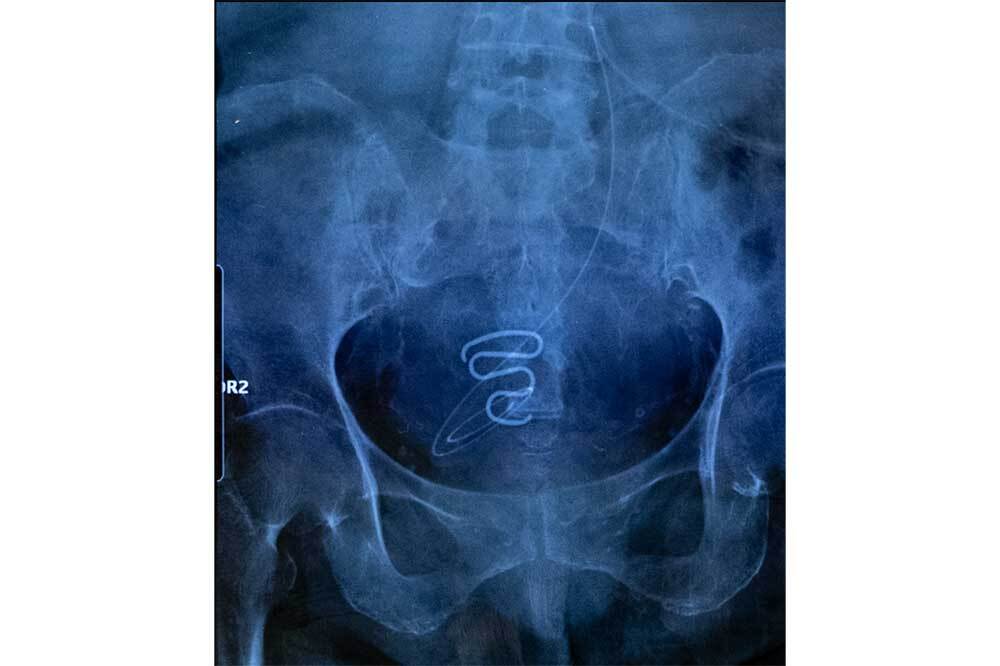

Yarışmada 2024 yılının fotoğrafçısı, belgesel kategorisine Spiralkampagnen (Sprial Kampanyası) başlıklı serisiyle katılan Fransız fotoğrafçı Juliette Pavy oldu. Ödüllerin açıklanmasından sonra yapılan basın toplantısında Pavy'i kazanan projesi hakkında şunları söyledi: "'Grönlandlı kadınların zorla kısırlaştırılması konusundaki çalışmalarım için verilen bu ödül için çok teşekkür ederim.Neredeyse yarım yüzyıl boyunca susturulanlara bir ses vermeyi umuyorum. Bu hikayeyi belgeleyerek, İnuit kadınlarına yönelik şiddet ve zorla kısırlaştırmanın sosyal ve psikolojik yansımaları konusunda farkındalık yaratmayı da umuyorum."